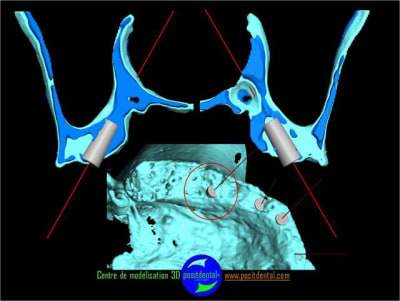

Le guide chirurgical, positionneur d’implants reste en place jusqu’à la pose des implants.

cicatrisation gingivale, suite expansion